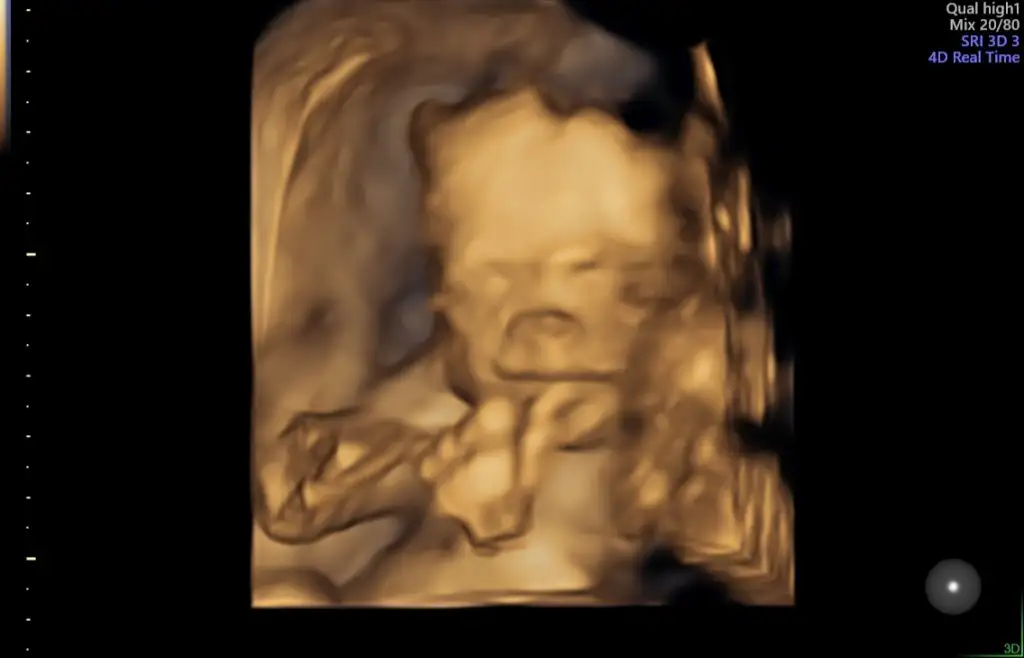

Bu da benim miniğim kızlar 😍 en güzel haftalara geldik artık galiba. Rabbim hepimize sağ sağlim kavuşmayı nasip etsin 🙏🙏

Eklentiler

• 20211231_125134.webp

20211231_125134.webp

13,2 KB · Görüntüleme: 66